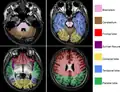

Brain regions on T1 MRI

Brain regions on T1 MRI -